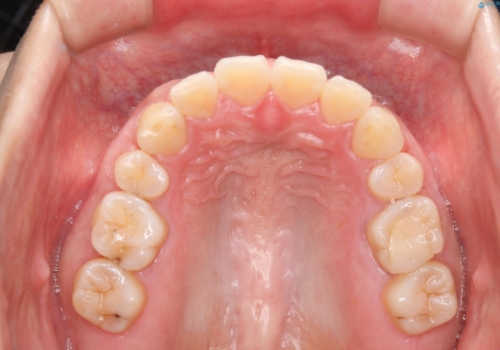

- 前歯のがたつきが気になるとご相談にいらした方です。当初は前歯の部分矯正をご希望されていましたが、全体的に整えることで審美的、機能的な歯並びとなりました。

当初は上顎前歯のみの部分矯正をご希望されていましたが、部分的に前歯のみを並べると出っ歯感がつよくなり、食事もしづらくなる可能性をお伝えしました。全顎的な矯正治療により、審美的、機能的な歯並びとなりました。